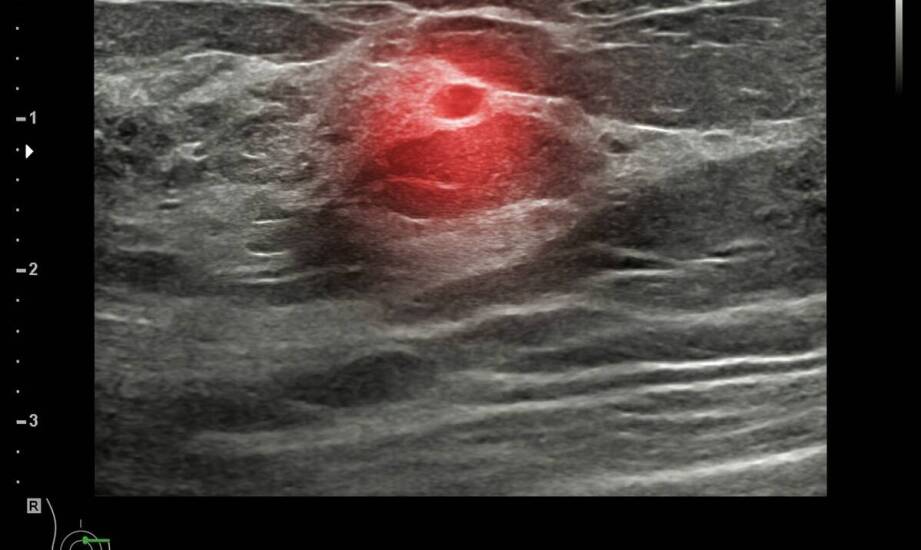

Rozpoznanie opiera się na ocenie źrenicy i przejrzystości ośrodków optycznych. W gabinecie stosuje się m.in. badanie w lampie szczelinowej oraz ocenę odruchu źrenicznego na światło. U niemowląt wykorzystuje się metody dostosowane do wieku, w tym ocenę fiksacji i śledzenia bodźców wzrokowych.

W wybranych sytuacjach, zwłaszcza przy jednostronnej leukokorii, konieczne jest różnicowanie z innymi przyczynami białej źrenicy. Decyzja o rodzaju badań dodatkowych zależy od obrazu klinicznego i wieku dziecka.